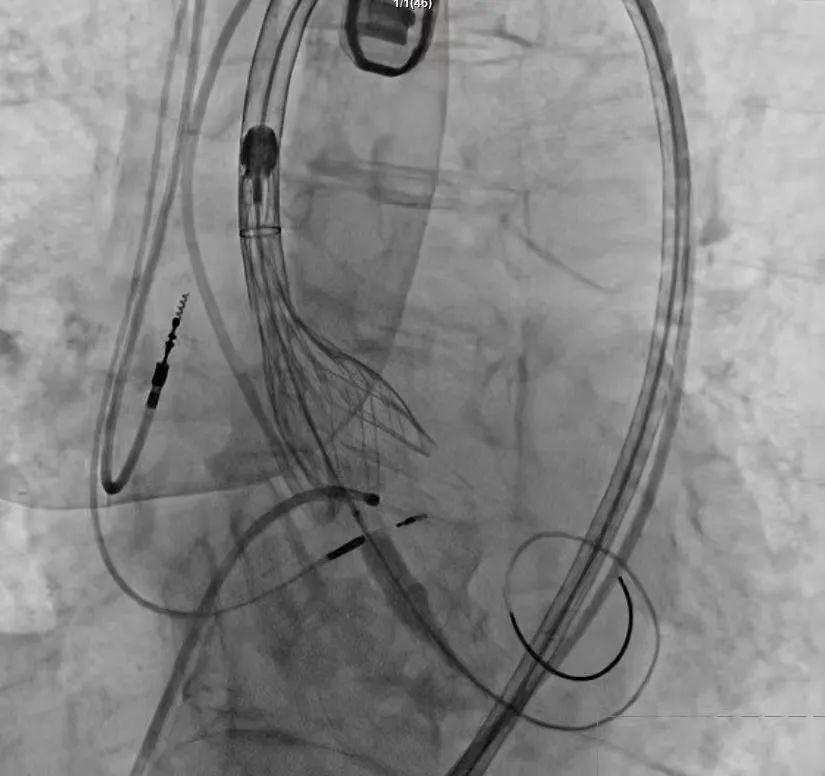

手术过程严谨有序:经术前精准评估与周密准备,团队成功送入预先装载的自膨式支架瓣膜输送系统,顺利完成过弓、跨瓣操作;经造影定位后,在180bpm快速起搏下精准释放瓣膜。瓣膜释放后,术中实时超声显示根部瓣架形态良好、启闭正常,瓣叶中心及瓣周未见反流;造影显示瓣膜位置满意、形态良好,冠脉显影清晰,入路血管无损伤,历经90分钟后,手术圆满成功。

术中影像